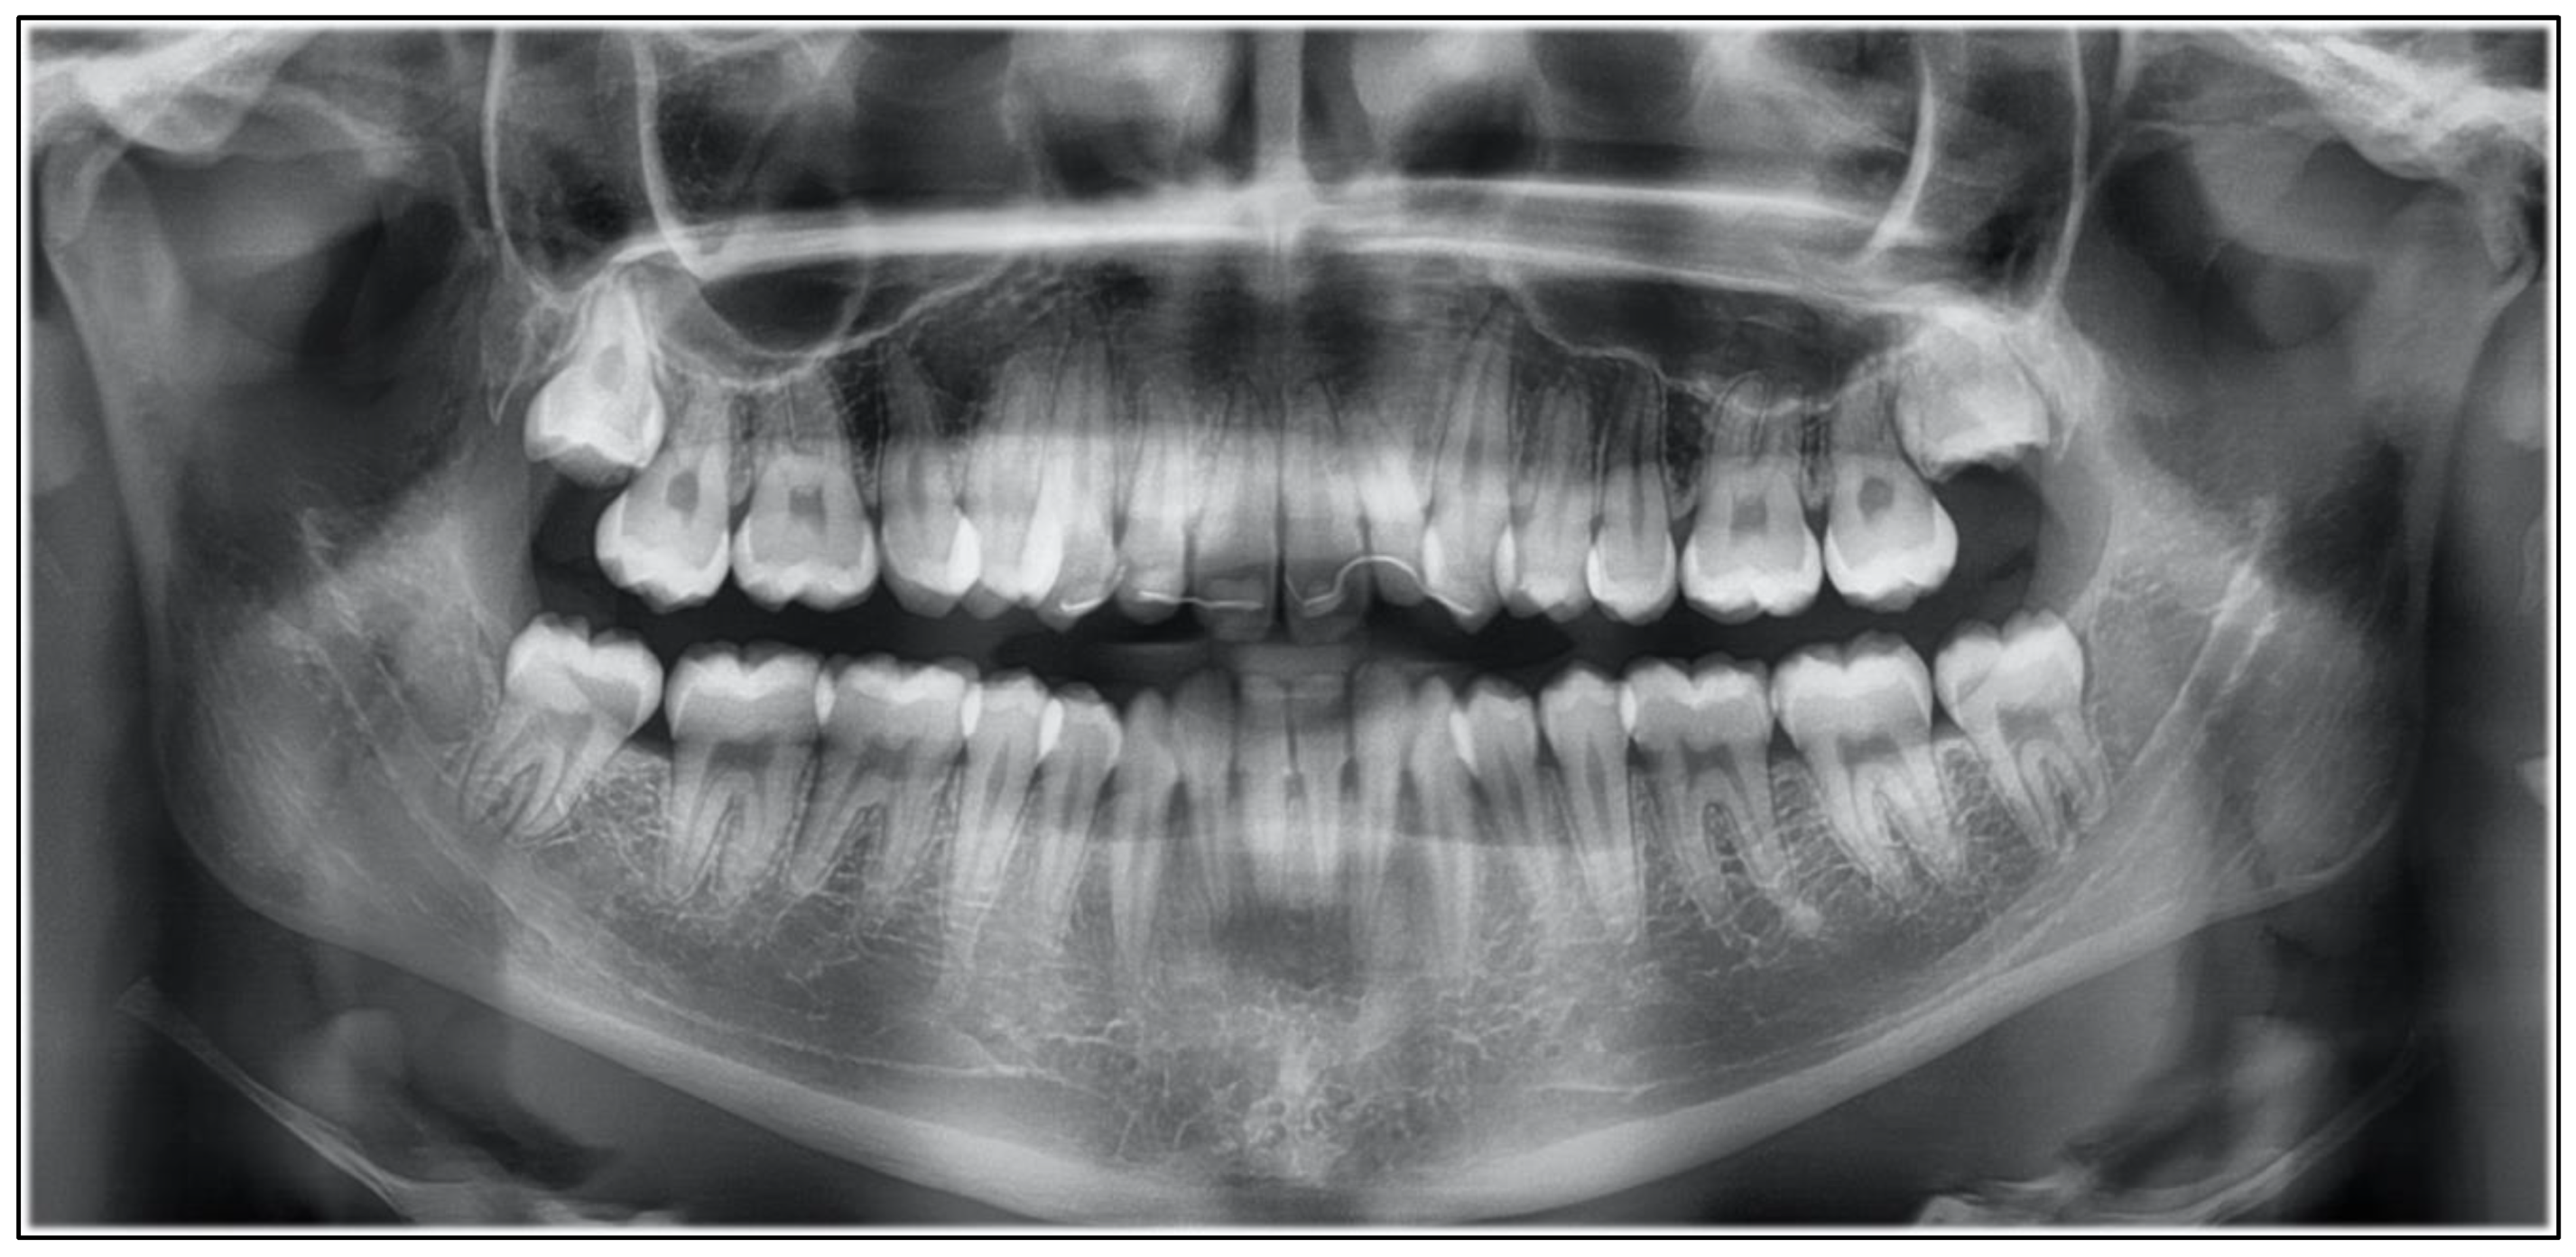

2. Case Report

2.2. Treatment Progress